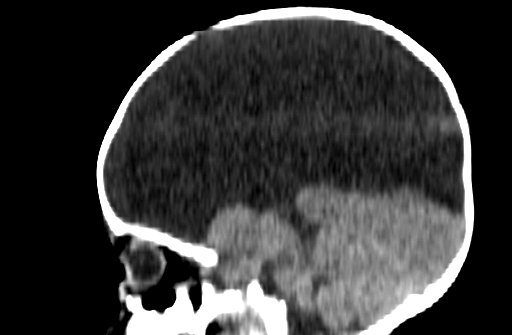

Hydrancephaly

• Destruction of cerebral hemispheres and replaced with fluid

• Basically bilateral large MCA infarcts

• Absence (may have some small residual tissue) of the cerebral hemispheres

• The thalami and posterior fossa are typically preserved

• Falx typically present -it is an infarct not midline cleavage issue!

• DDx - severe hydrocephalus, L1CAM disease, oters